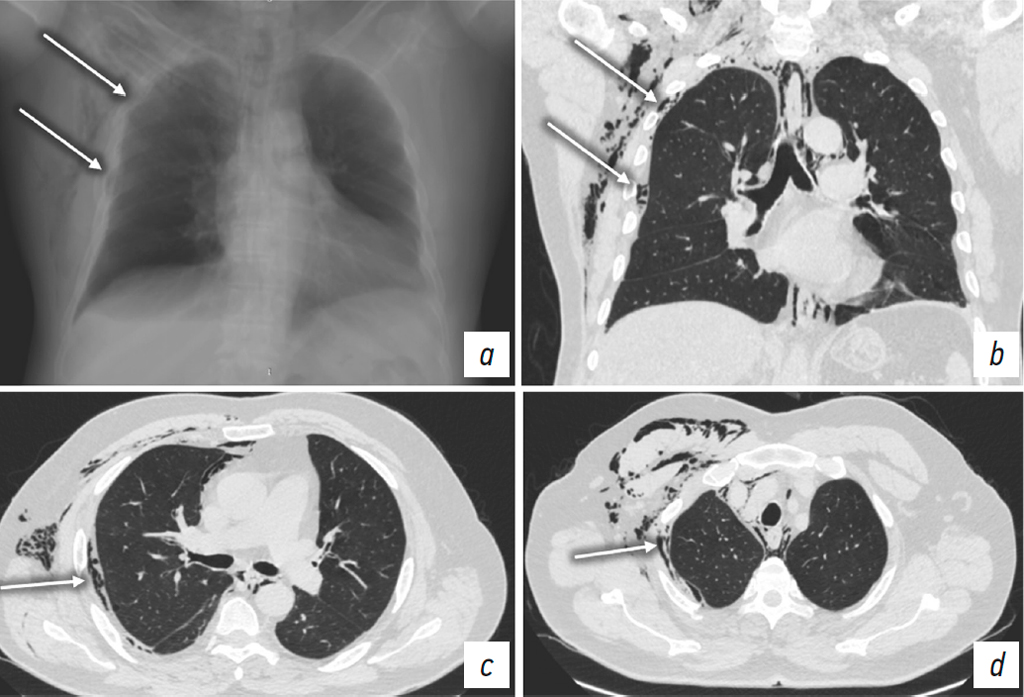

Furthermore, unilateral coexistence of pneumothorax and EPS emphysema was observed in five patients (Fig. 6). In three of these patients, the drainage tube was positioned in the EPS, which resulted in failure to drain the pleural cavity, progressive clinical deterioration, and the development of subcutaneous emphysema (Fig. 7). In one case, severe EPS emphysema was associated with respiratory failure (Fig. 8). US revealed findings characteristic of pneumothorax, including the absence of pleural sliding (Fig. 9).

Fig. 7. Patient T. Chest CT: a–c, axial plane at different levels in the craniocaudal direction; d, sagittal plane through the right hemithorax. Right-sided pneumothorax (black arrows). Pneumomediastinum. Extrapleural emphysema on the right side (white arrows) with a chest drain tube (dashed arrows).

Рис. 7. Пациент Т. КТ органов груди: а–c — аксиальная плоскость на разных уровнях в краниокаудальном направлении; d — сагиттальная плоскость, правый гемиторакс. Правосторонний пневмоторакс (черные стрелки). Пневмомедиастинум. Эмфизема ЭПП справа (белые стрелки) с дренажной трубкой (пунктирные стрелки).